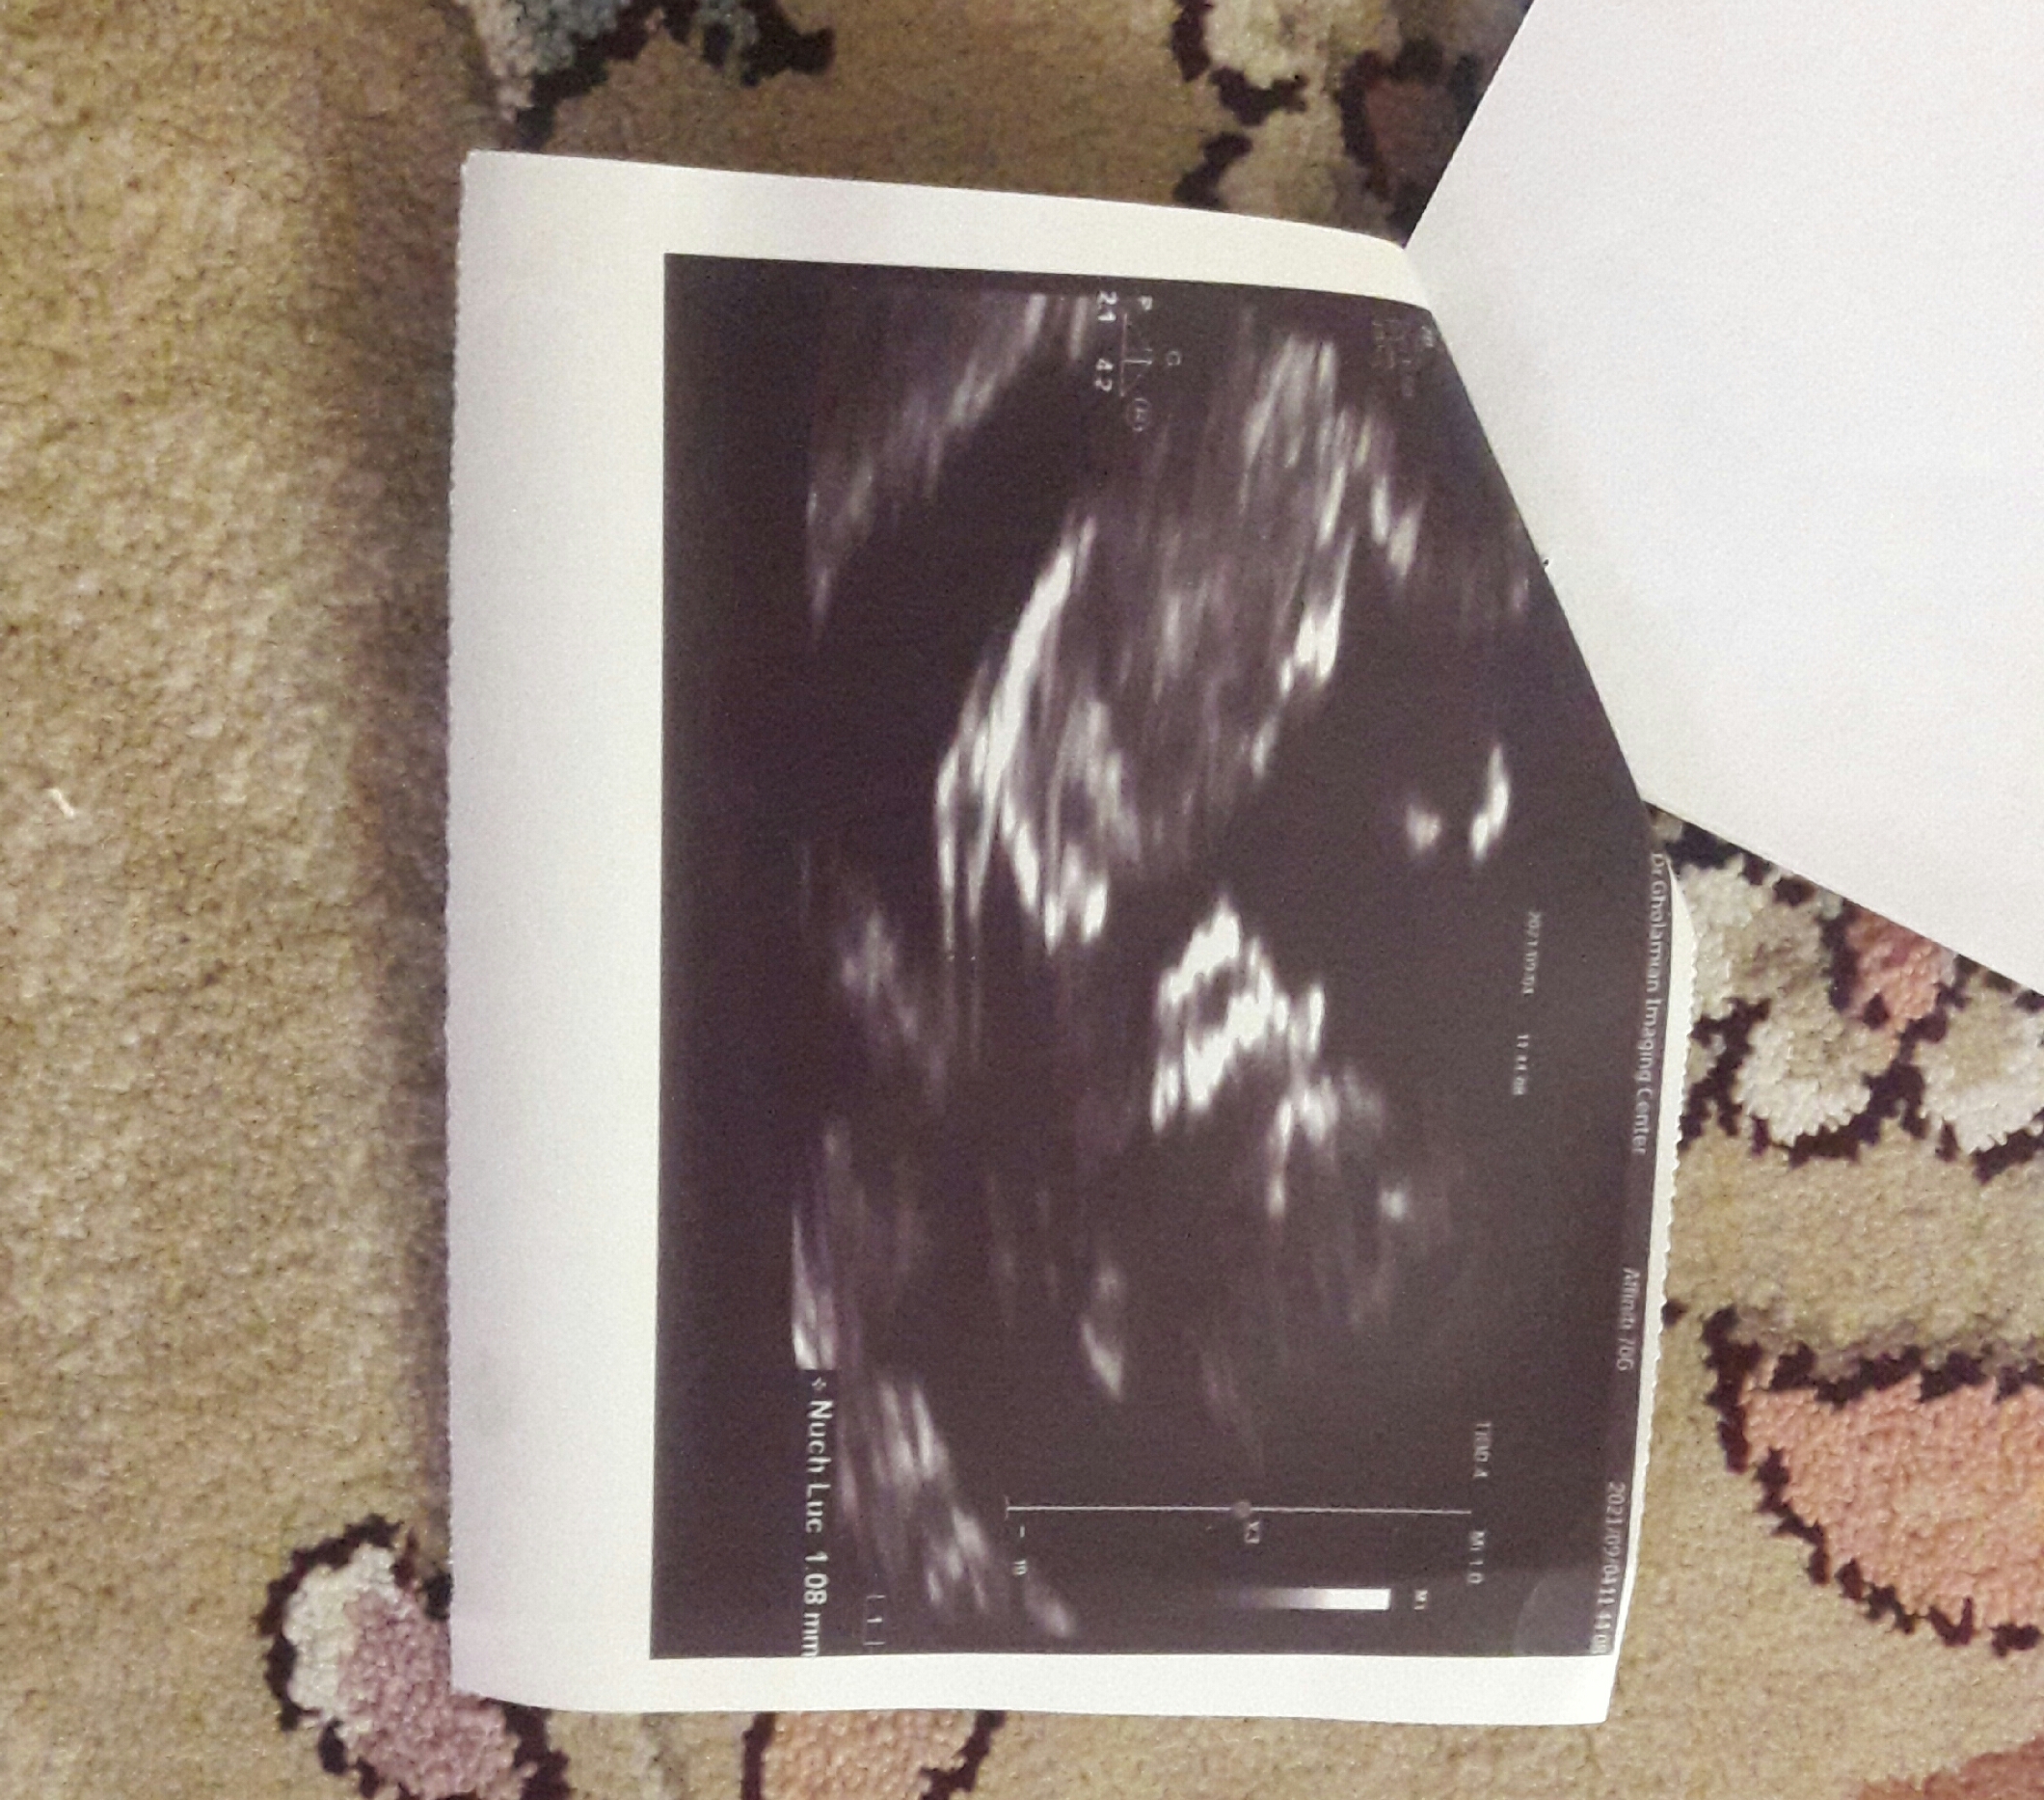

فرق اینا فقط جنسیه چطوری فرقشونو فهمیدی من تفاوتی نمیبینم چرا دور اون تفاوت خط بکش منم بدونم

دقت کن بالایی قسمت پیشونی مثل زاویه ۹۰درجه هست اما پایینی کاملا گرده